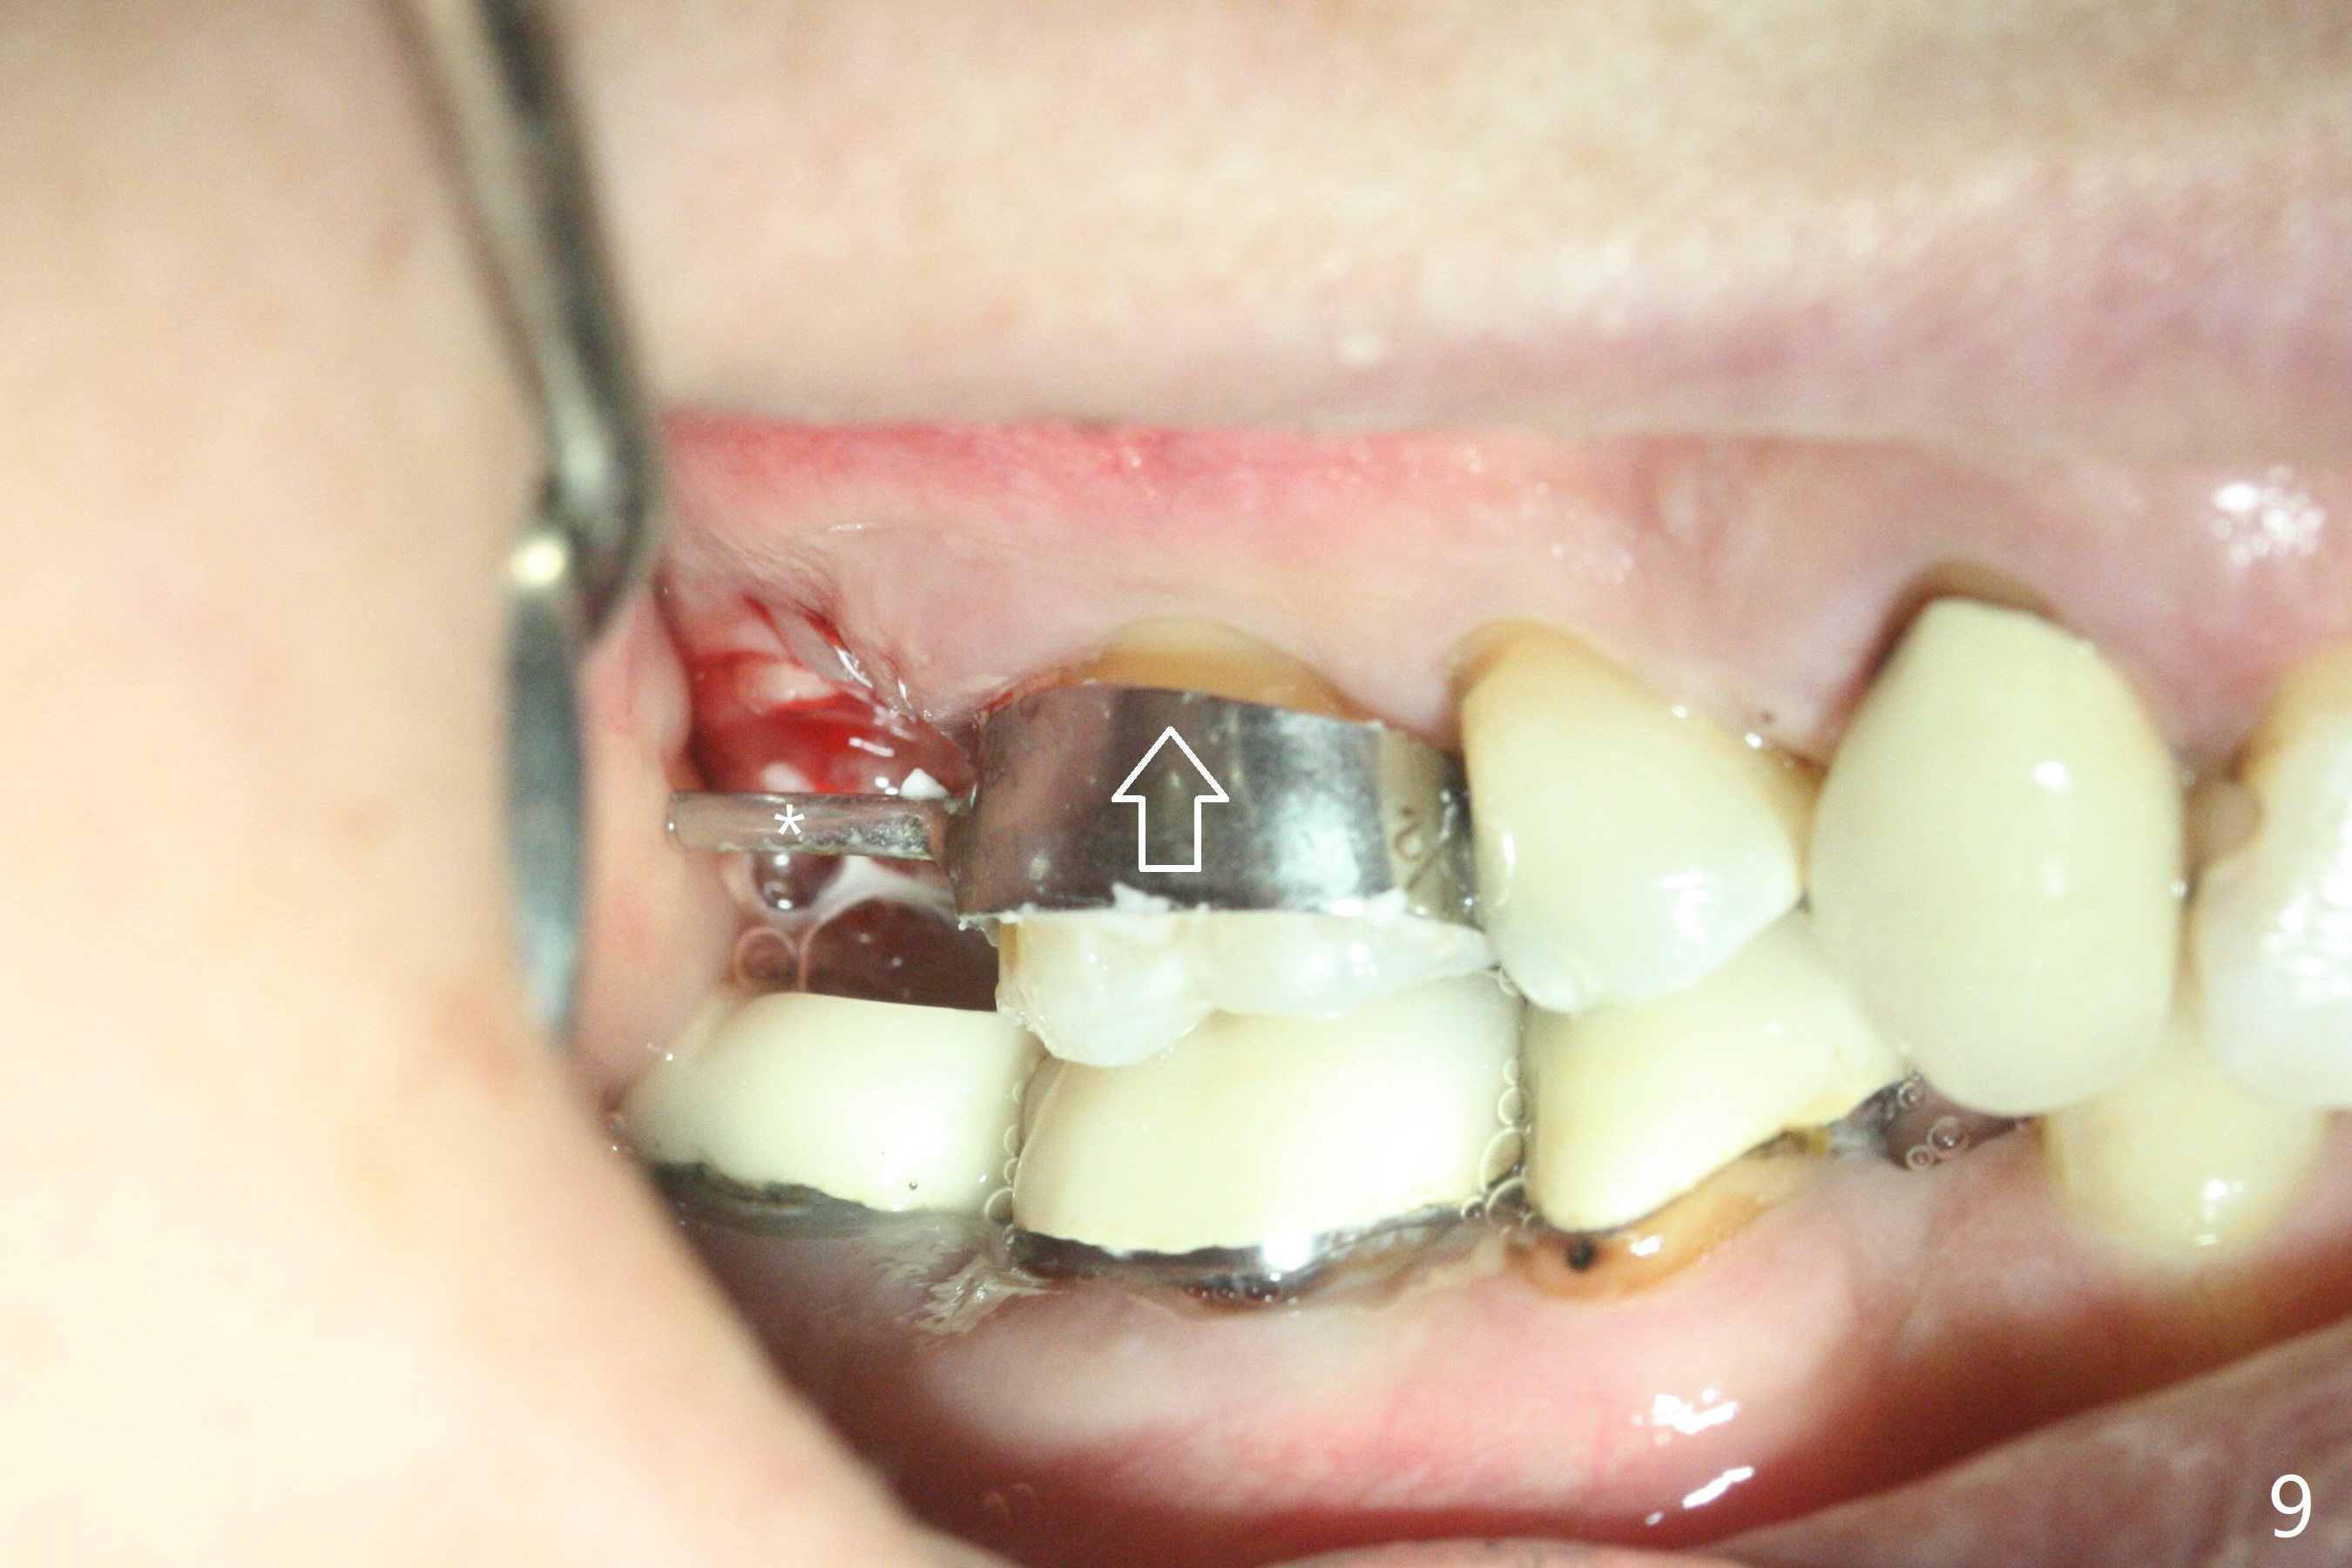

第二磨牙位点保留后,牙周敷料容易脱落,尤其上颌,本文介绍一种方法增加固位。右上七严重牙髓牙周综合征,拔出后使用刮匙除去骨面肉芽组织,颊侧骨板缺失,附着在颊侧粘骨膜上的肉芽组织使用一种叫Stieglitz angled, diamond splinter forceps (德国产,图一,二)撕下来。彻底清除炎性组织必须多次刮治,之间塞入带有灭滴灵(图三:粉剂)和1比50,000肾上腺素局麻药纱布(图四)止血,取出纱布,牙槽窝视野好,继续去除残余的肉芽组织。牙槽窝底部穿孔,用无齿刮匙稍微扩大穿孔后,使用图五下面小的骨粉输送器,将少量骨粉(粘性)送到穿孔处,推入上颌窦(图七:S),之后使用大的骨粉输送器(图五上面),把大量骨粉送到牙槽窝,使用图六上面大的,长的充填器,压实骨粉(图七),骨粉表面放置PRF膜和不可吸收膜(图八),在第一磨牙时安置粘固一个间隙维持器(图九,十),最后铺上牙周敷料(图十一),检查咬合空间,没有干扰。There are sign and symptom of sinusitis 1 week postop; large amount of bone graft retains in the socket by the periodontal dressing and spacer (Fig.12). The sinus membrane (Fig.7 immediate postop) thickens 1 week postop (Fig.13). Augmentin and Medrol Dose Pak are prescribed. 上颌窦炎一周后消失,腭侧牙周敷料丢失,伤口好像正常愈合(图十四)。术后三周牙周敷料由于大量水枪冲洗脱落(图十五)。因为病人需要离城两个月,间隙保持器撤除(图十六),不可吸收膜腭侧稍微外翻 (<),可能有利于术后五周自行脱落。No Deviation SP 下一个病例 位点保留后Xin 导板与张口度 第一磨牙即种 Wei, DDS, PhD, MS 1st edition 09/17/2020, last revision 04/30/2021